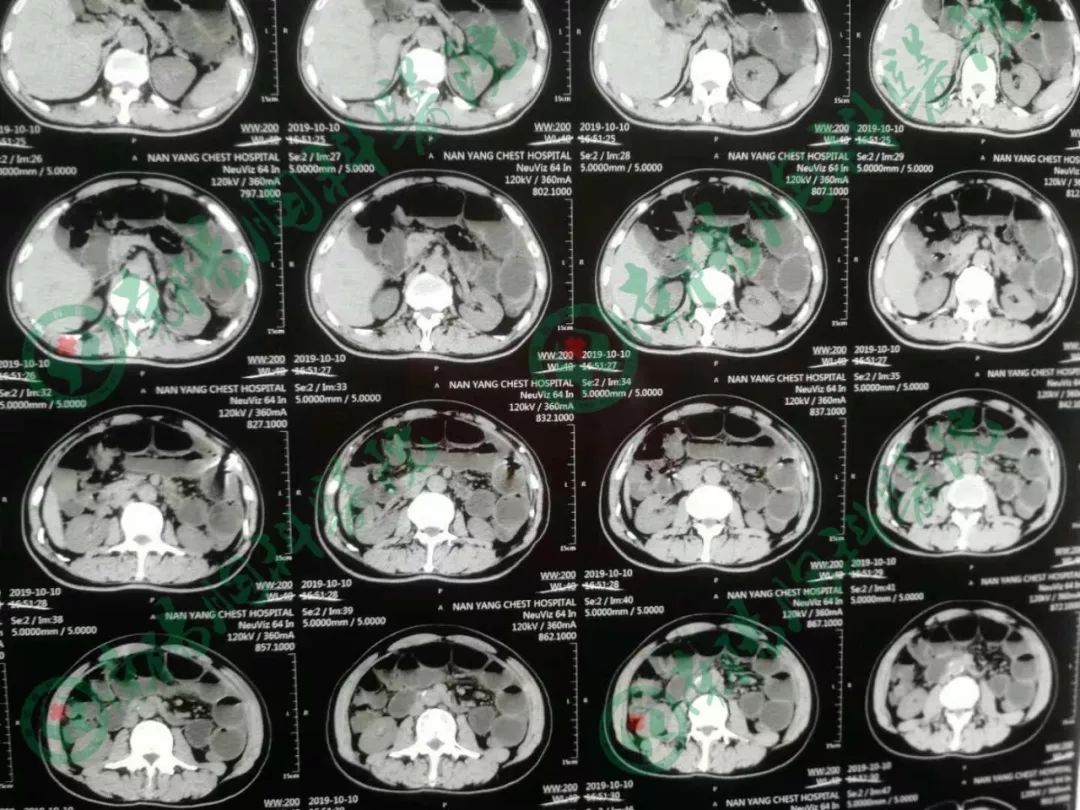

患者经过立位DR和CT检查均提示肠管高度扩张,多发阶梯状液平,病情非常棘手。

告知急诊手术,术中探查见小肠高度扩张,末段回肠扭转粘连于盆底骶前,放射性肠炎改变,呈冻结状,部分肠管受压坏死,行末段冻结扭转回肠切除术,小肠造瘘术,术后病人生命体征平稳,安返ICU。